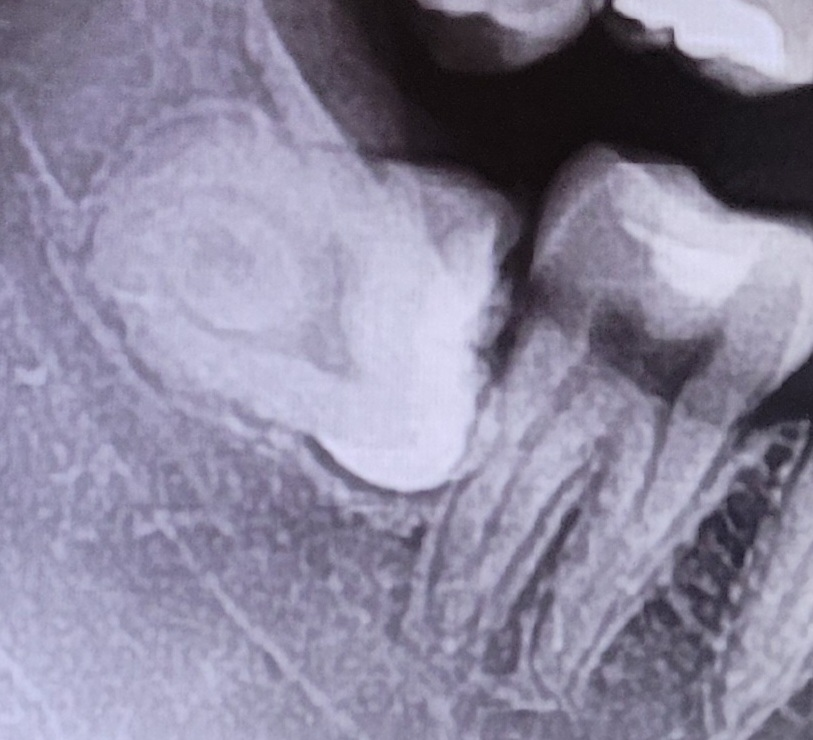

제 치아 엑스레이입니다

아프진 않은데 빈 잇몸에 찔끔 이가 돋아난 게 보여서 치과가서 확인해봤더니 매복사랑니고, 웬만하면 뽑으라고 해서요..

제 치아가 신경에 걸쳐있어서 큰병원에서 하라고 하고, 여러 글 찾아보니 너무 무서워서ㅠㅠ뽑아야할지 조언 부탁드려요..

제 사랑니 많이 깊고 까다로워 보이나요?

그리고 발치시 신경마비 가능성도 있다던데....너무 무서워요ㅜㅜ

사진 상에서 보았을 때, 발치가 까다로운 것은 아닙니다. 하지만 아시는 것처럼 해당 사랑니는 신경과 매우 근접해 보입니다. 물론 정확히 신경과 얼마나 근접한지는 dental-CT 등을 촬영해보아야 겠지만 높은 확률로 가깝거나 붙어 있을 수 있습니다. 이러한 경우에는 상급병원에서 뽑는 것이 맞으며, 무리하게 뽑지 않고 뿌리 등은 남겨둘 수도 있습니다. 까다롭고 힘든 것은 아니나 어느정도의 리스크는 있다 보여집니다.